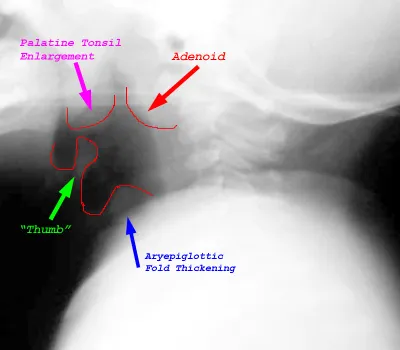

- Acute Epiglottitis: Medical emergency! Characterized by dysphagia, drooling, and distress. Cherry-red epiglottis.